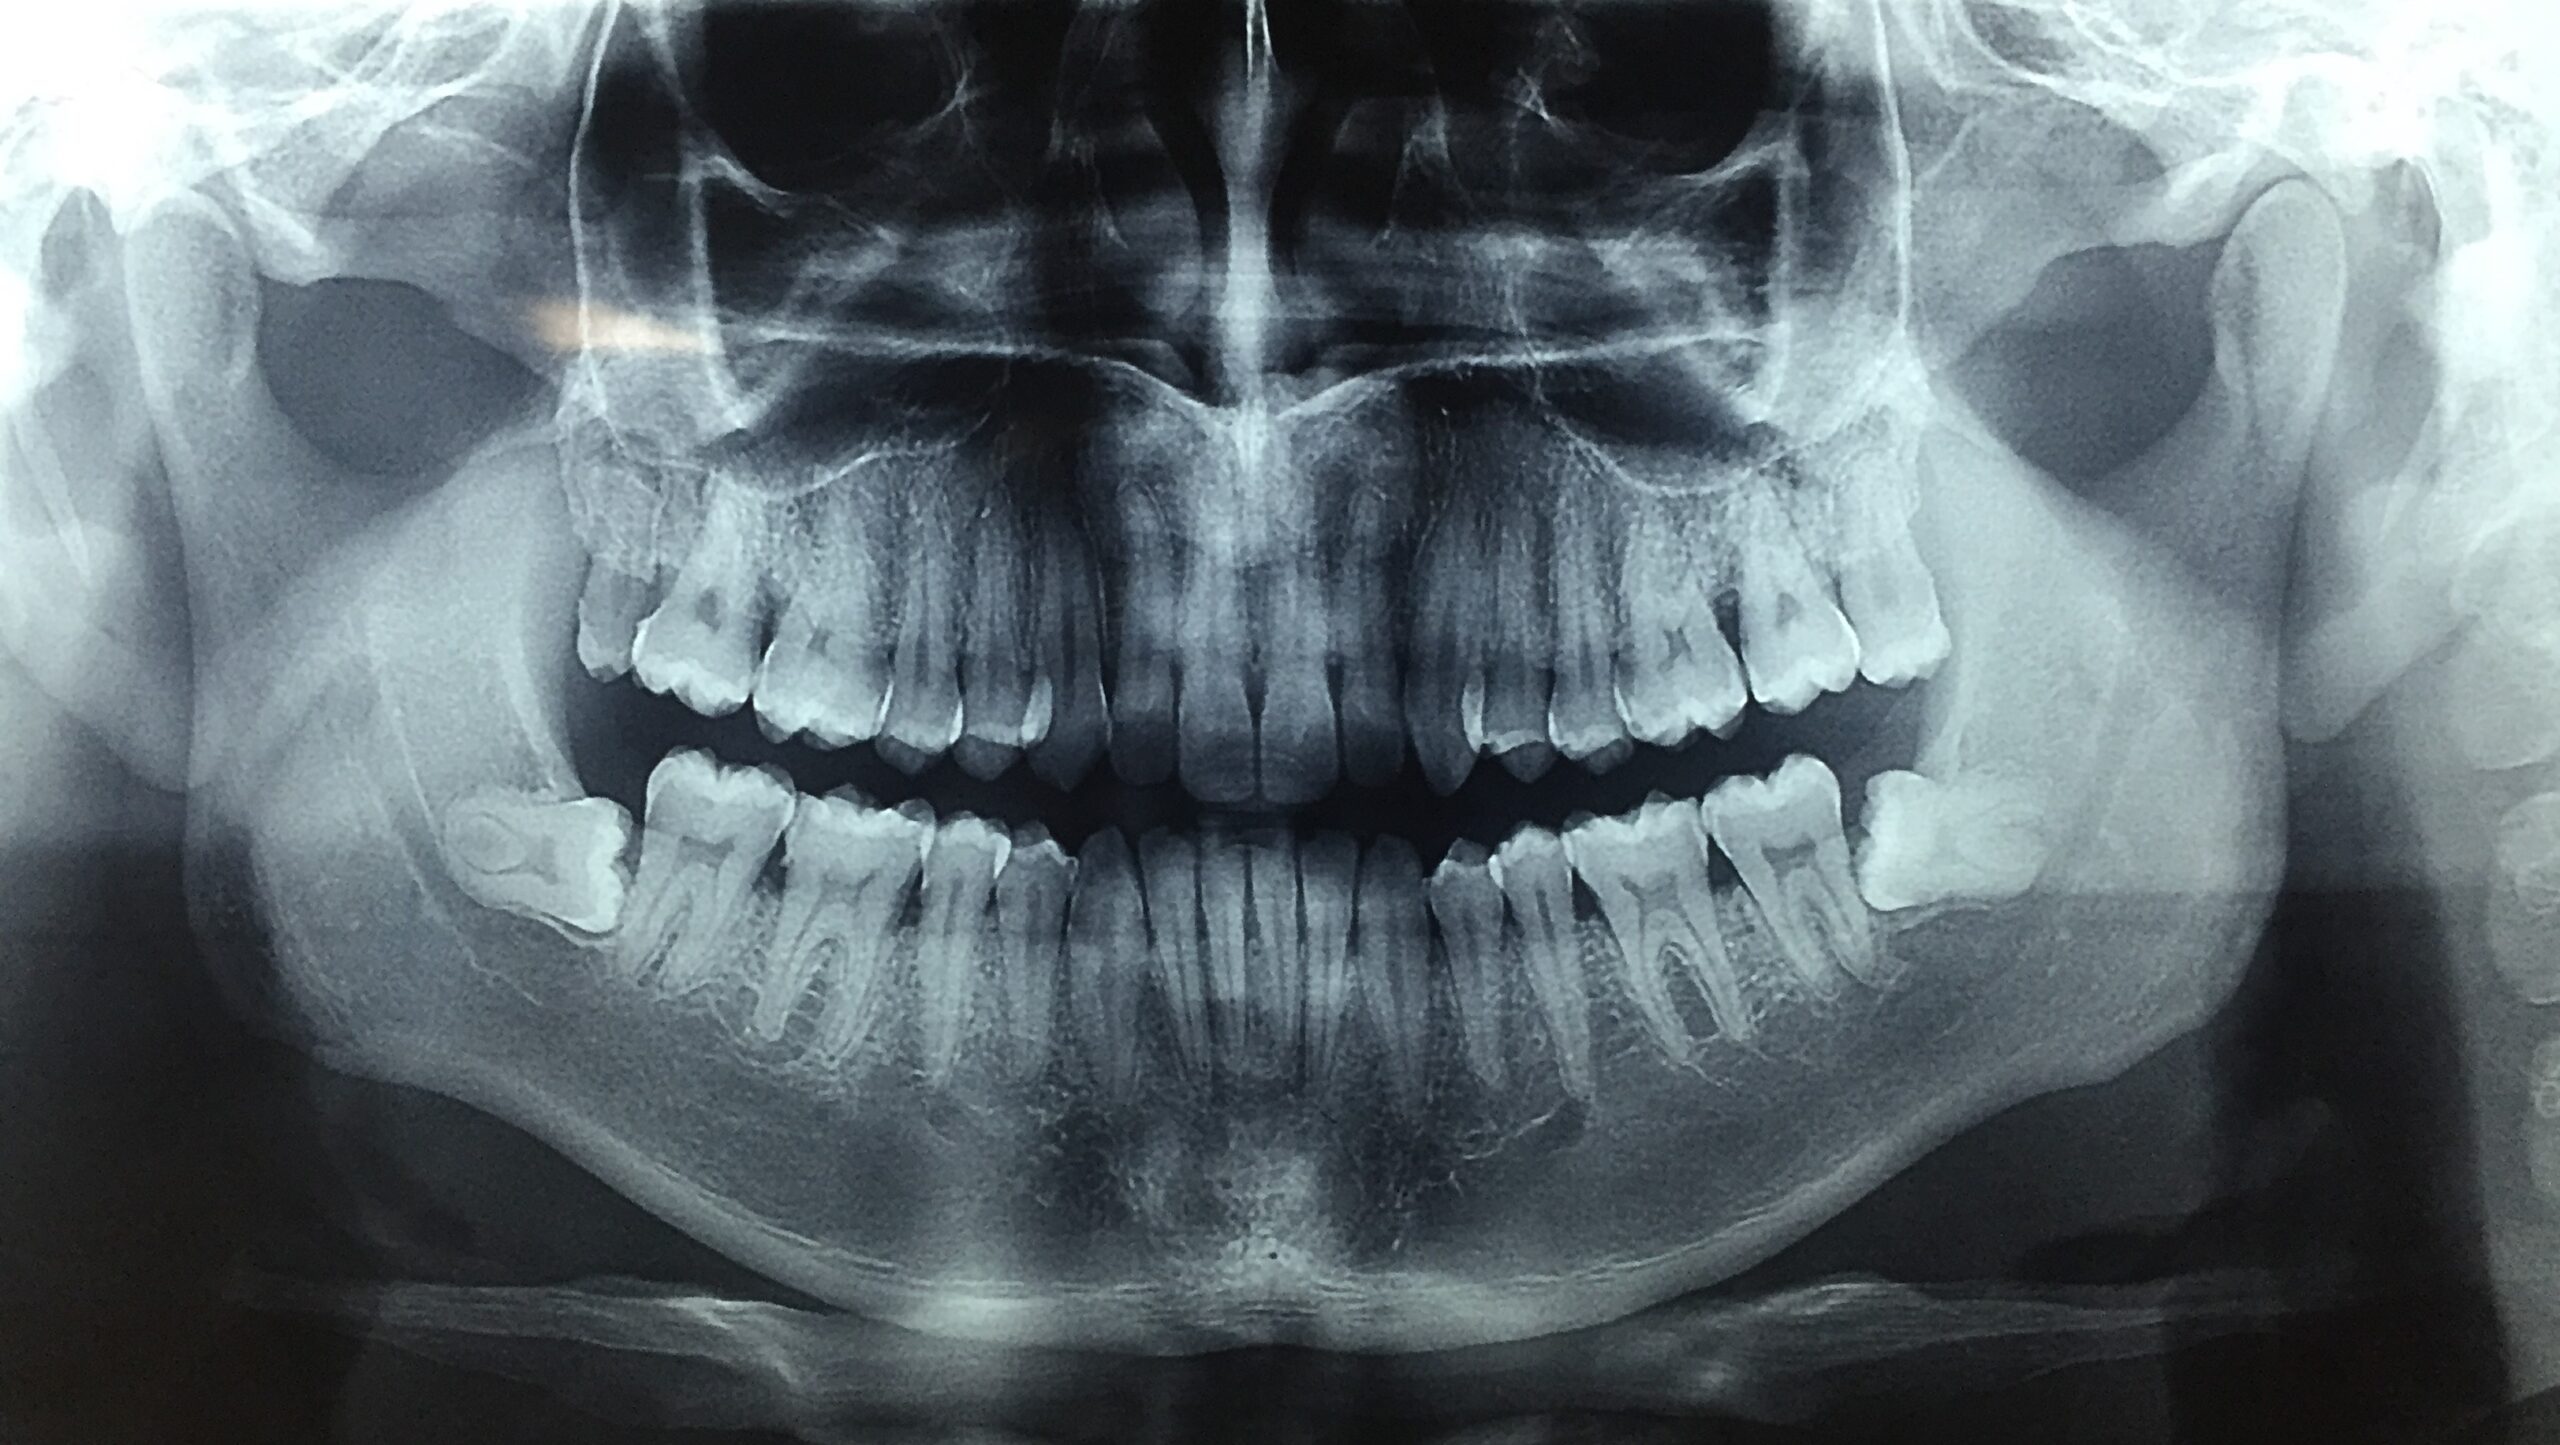

La programación virtual de cirugía ortognática y de implantes dentarios ha revolucionado la planificación y ejecución de tratamientos dentales y maxilofaciales, permitiendo una mayor precisión, predicción de resultados y una mejor experiencia para el paciente. A través de tecnologías avanzadas de simulación, es posible planificar procedimientos quirúrgicos de manera virtual antes de realizar cualquier intervención física. Programación Virtual en Cirugía Ortognática La cirugía ortognática es un procedimiento quirúrgico que se realiza para corregir las deformidades de los huesos de la mandíbula y el maxilar, mejorando tanto la funcionalidad como la estética facial. La programación virtual en esta cirugía ofrece varias ventajas: Estas guías son fabricadas mediante impresión 3D y permiten una cirugía menos invasiva y con una recuperación más rápida. Diagnóstico 3D: Se utilizan imágenes en 3D, como las tomografías computarizadas (TC) o las radiografías panorámicas, para obtener una visualización precisa de la anatomía facial del paciente. La reconstrucción en 3D de la estructura ósea permite al cirujano planificar la cirugía de forma más detallada. Planificación virtual: Con el software de planificación virtual, los cirujanos pueden simular los movimientos de los huesos maxilares y mandibulares antes de la cirugía. Esto ayuda a determinar la cantidad exacta de desplazamiento que se debe realizar y permite predecir el resultado final en términos de alineación facial y funcionalidad masticatoria. Simulación de la cirugía: La cirugía se simula de forma virtual en el software, lo que permite probar diferentes opciones antes de decidir la más adecuada. La planificación puede incluir la posibilidad de realizar cambios en el diseño de la mandíbula, maxilar o incluso el uso de placas y tornillos para estabilizar los huesos después de la corrección. Guías quirúrgicas personalizadas: Con la ayuda de la programación virtual, se pueden crear guías quirúrgicas personalizadas que dirigen con precisión la colocación de los cortes en los huesos.